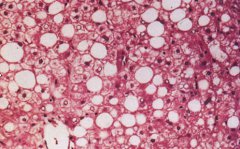

脂肪肝,是指由于各種原因引起的肝細(xì)胞內(nèi)脂肪堆積過多的病變。脂肪性肝病正嚴(yán)重威脅國人的健康,成為僅次于 病毒性肝炎 的第二大肝病。脂肪肝是一種常見的臨床現(xiàn)象,而非一種獨(dú)立的疾...

大約有一半的肥胖者患有脂肪肝。脂肪肝又稱為肝脂肪變性,是過多的脂肪堆積在肝臟內(nèi)形成的一種疾病。正常的肝臟內(nèi)僅僅含有小量脂肪,約占肝臟體積的4%~7%,其中的一半為甘油三酯,另...

在正常情況下,肝臟對(duì)人體內(nèi)物質(zhì)的分解、合成、解毒以及脂肪的代謝等一系列精細(xì)而又復(fù)雜的操作始終保持著動(dòng)態(tài)平衡。脂肪肝是由于各種原因引起的肝細(xì)胞內(nèi)脂肪堆積過多的病變。重度脂肪...